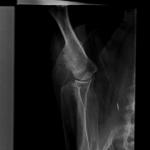

Здравствуйте! У нашей французской бульдожки с лета непонятная хромота на правую переднюю лапку. Она у неё как бы в сторону отъезжает, стоит на всех четырёх лапках но на эту полный упор не делает. Когда стоит или сидит, может эту лапку просто подогнуть. Хромает то меньше то больше, был период что практически было хорошо. Бывало, что когда она потянется лёжа, или пытается встать то взвизгивает но это не всё время. Девочке 10 лет, никаких травм не было. От корма не отказывается, ведёт себя нормально. Давали: когда очень болела лапка, петкам 0.5, кололи пару раз айнил; затем прошло время, другой врач назначил на неделю где то травматин, хондартрон, прокололи.Потом купили хондропротектор Артрогликан , сейчас заканчиваем курс, делаем массаж.Ездили в другой город чтобы сделали рентген, сделали нам 2 проекции, врач визуально осмотрев собаку сказал что с правой стороны уменьшилась мышечная масса, нужно делать упражнения и массаж что мы сейчас и делаем. Также осматривал и пальпировал её лапку, тянул в разные стороны, она не пискнула даже.Что конкретно с лапкой он не знает, сказал сделать рентген через месяц ещё раз. Посмотрите пожалуйста снимки, на что это может быть похоже? Очень переживаем, на сколько может быть серьёзно то что на снимках? Очень жду ответ!

По снимкам ничего не вижу, во всяком случае, грубой патологии точно нет. Но снимки нужно смотреть глазами, а не по фото. Если есть возможность, отнесите хирургу или травматологу в свою больницу, пусть внимательно посмотрит суставные поверхности.

Если по снимкам ничего определить не удастся, то нужно делать МРТ сустава.

Здравствуйте, спасибо большое что ответили! Наш врач к которому изначально ходим выходит на работу через неделю, ждём его. Просто врач который рентген делал пугал новообразованием , он только увидел остеофиты надкостницы и предположил либо воспаление либо ещё что хуже, но он не знает. Напугали в клинике, начитались в интернете про хондросаркому , очень за это переживаем, поэтому спрашиваем на что может быть похоже!

Я пересмотрел еще раз снимки с увеличением, и мне не очень нравится в/3 плечевой кости. Я не большой знаток анатомии костной системы собак, поэтому понять природу изменений мне трудно. Хочу Вам высказать мысль, что если у рентгенолога возникли какие-то подозрения, лучше было бы сделать и снимки здоровой лапы. Иногда бывает, что это сразу решает проблему.